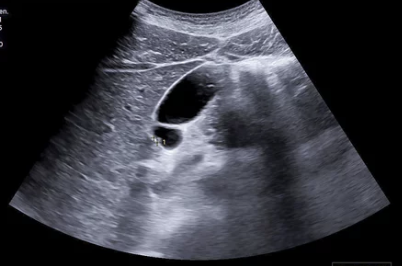

📌 1) 복부 초음파 검사

- 담낭 내 혹(종양)이나 담석 여부 확인 가능

- 간단한 검사이지만, 초기 담낭암을 발견하기 어려운 경우도 있음